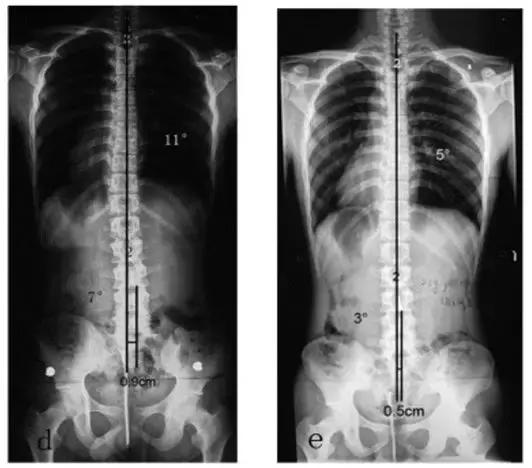

可以看下面这张图(图文引用于文献【1】),患者为右侧L5-S1间盘突出,术前脊柱侧弯非常严重!上半身重心偏移也非常严重!

下方左图是术后即刻的,可以看到侧弯已经大部分恢复了!下方右图是术后2.5年的,侧弯基本上完全恢复!

相对而言,青少年患者的柔韧性要好一些,因此更容易因为腰突而患脊柱侧弯,但同时其术后的恢复效果也会更好一些!

少部分患者如果术前拖的时间长了,可能在术后两年也得不到完全的恢复,但侧弯也会比术前要好很多。